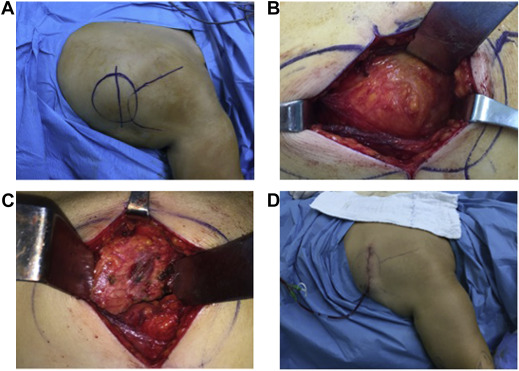

Surgical indications were defined as tumor larger than 5 cm in size and symptoms related to lesion. Marginal resection was performed by 2 senior orthopedic oncologists (authors 1 and 2) with the same exposure. Under general anesthesia, with patient in prone position, ipsilateral arm was draped freely to have better localization of lesion. Latissimus dorsi muscle was split with transverse incision over the lesion, and serratus anterior muscle was accessed. Hard, white tissue with uncertain margin that was firmly attached to serratus anterior and periosteum of ribs was separated using electrocautery, and marginal resection was performed. Suction drain was inserted after resection with careful control of hemorrhage (Fig. 1 ). Drain was kept in place for at least 48 h. Patients wore arm sling for 15 days after surgery. Subsequently, passive movements were initiated; active, full range of joint motion (ROM) was allowed in first postoperative month. Follow-up was conducted at 15 days, first month, third month, and at intervals of 3 months for the first 1.5 years after procedure. Recurrence was evaluated with clinical examination at each visit, followed by ultrasound (US) if there was suspected lesion.

Fig. 1. Surgical technique. (A) Mass is made clearly visible by abducting and elevating the arm in the prone position, and (B) is reached by passing through latissimus dorsi and serratus anterior muscles. (C) . Chest wall after resection. (D) Appearance after the wound was closed.

Study patients were 6 males (11.8%) and 45 females (88.2%). Average age was 55.33 ± 7.01 years (range: 41–69 years). Regarding professional occupation, 44 were housewives, 2 worked at desk jobs, and 5 were manual laborers. All of the lesions were located in inferior subscapular region, which is the typical location for ED. The most frequent presenting complaint was mass that could be clearly visualized with abduction and elevation of arm (90%) (Fig. 2 ), followed by pain (73.7%) during shoulder movement, and scapular snapping (65%). Average duration of symptoms was 11.21 ± 4.77 months (range: 4–26 months).